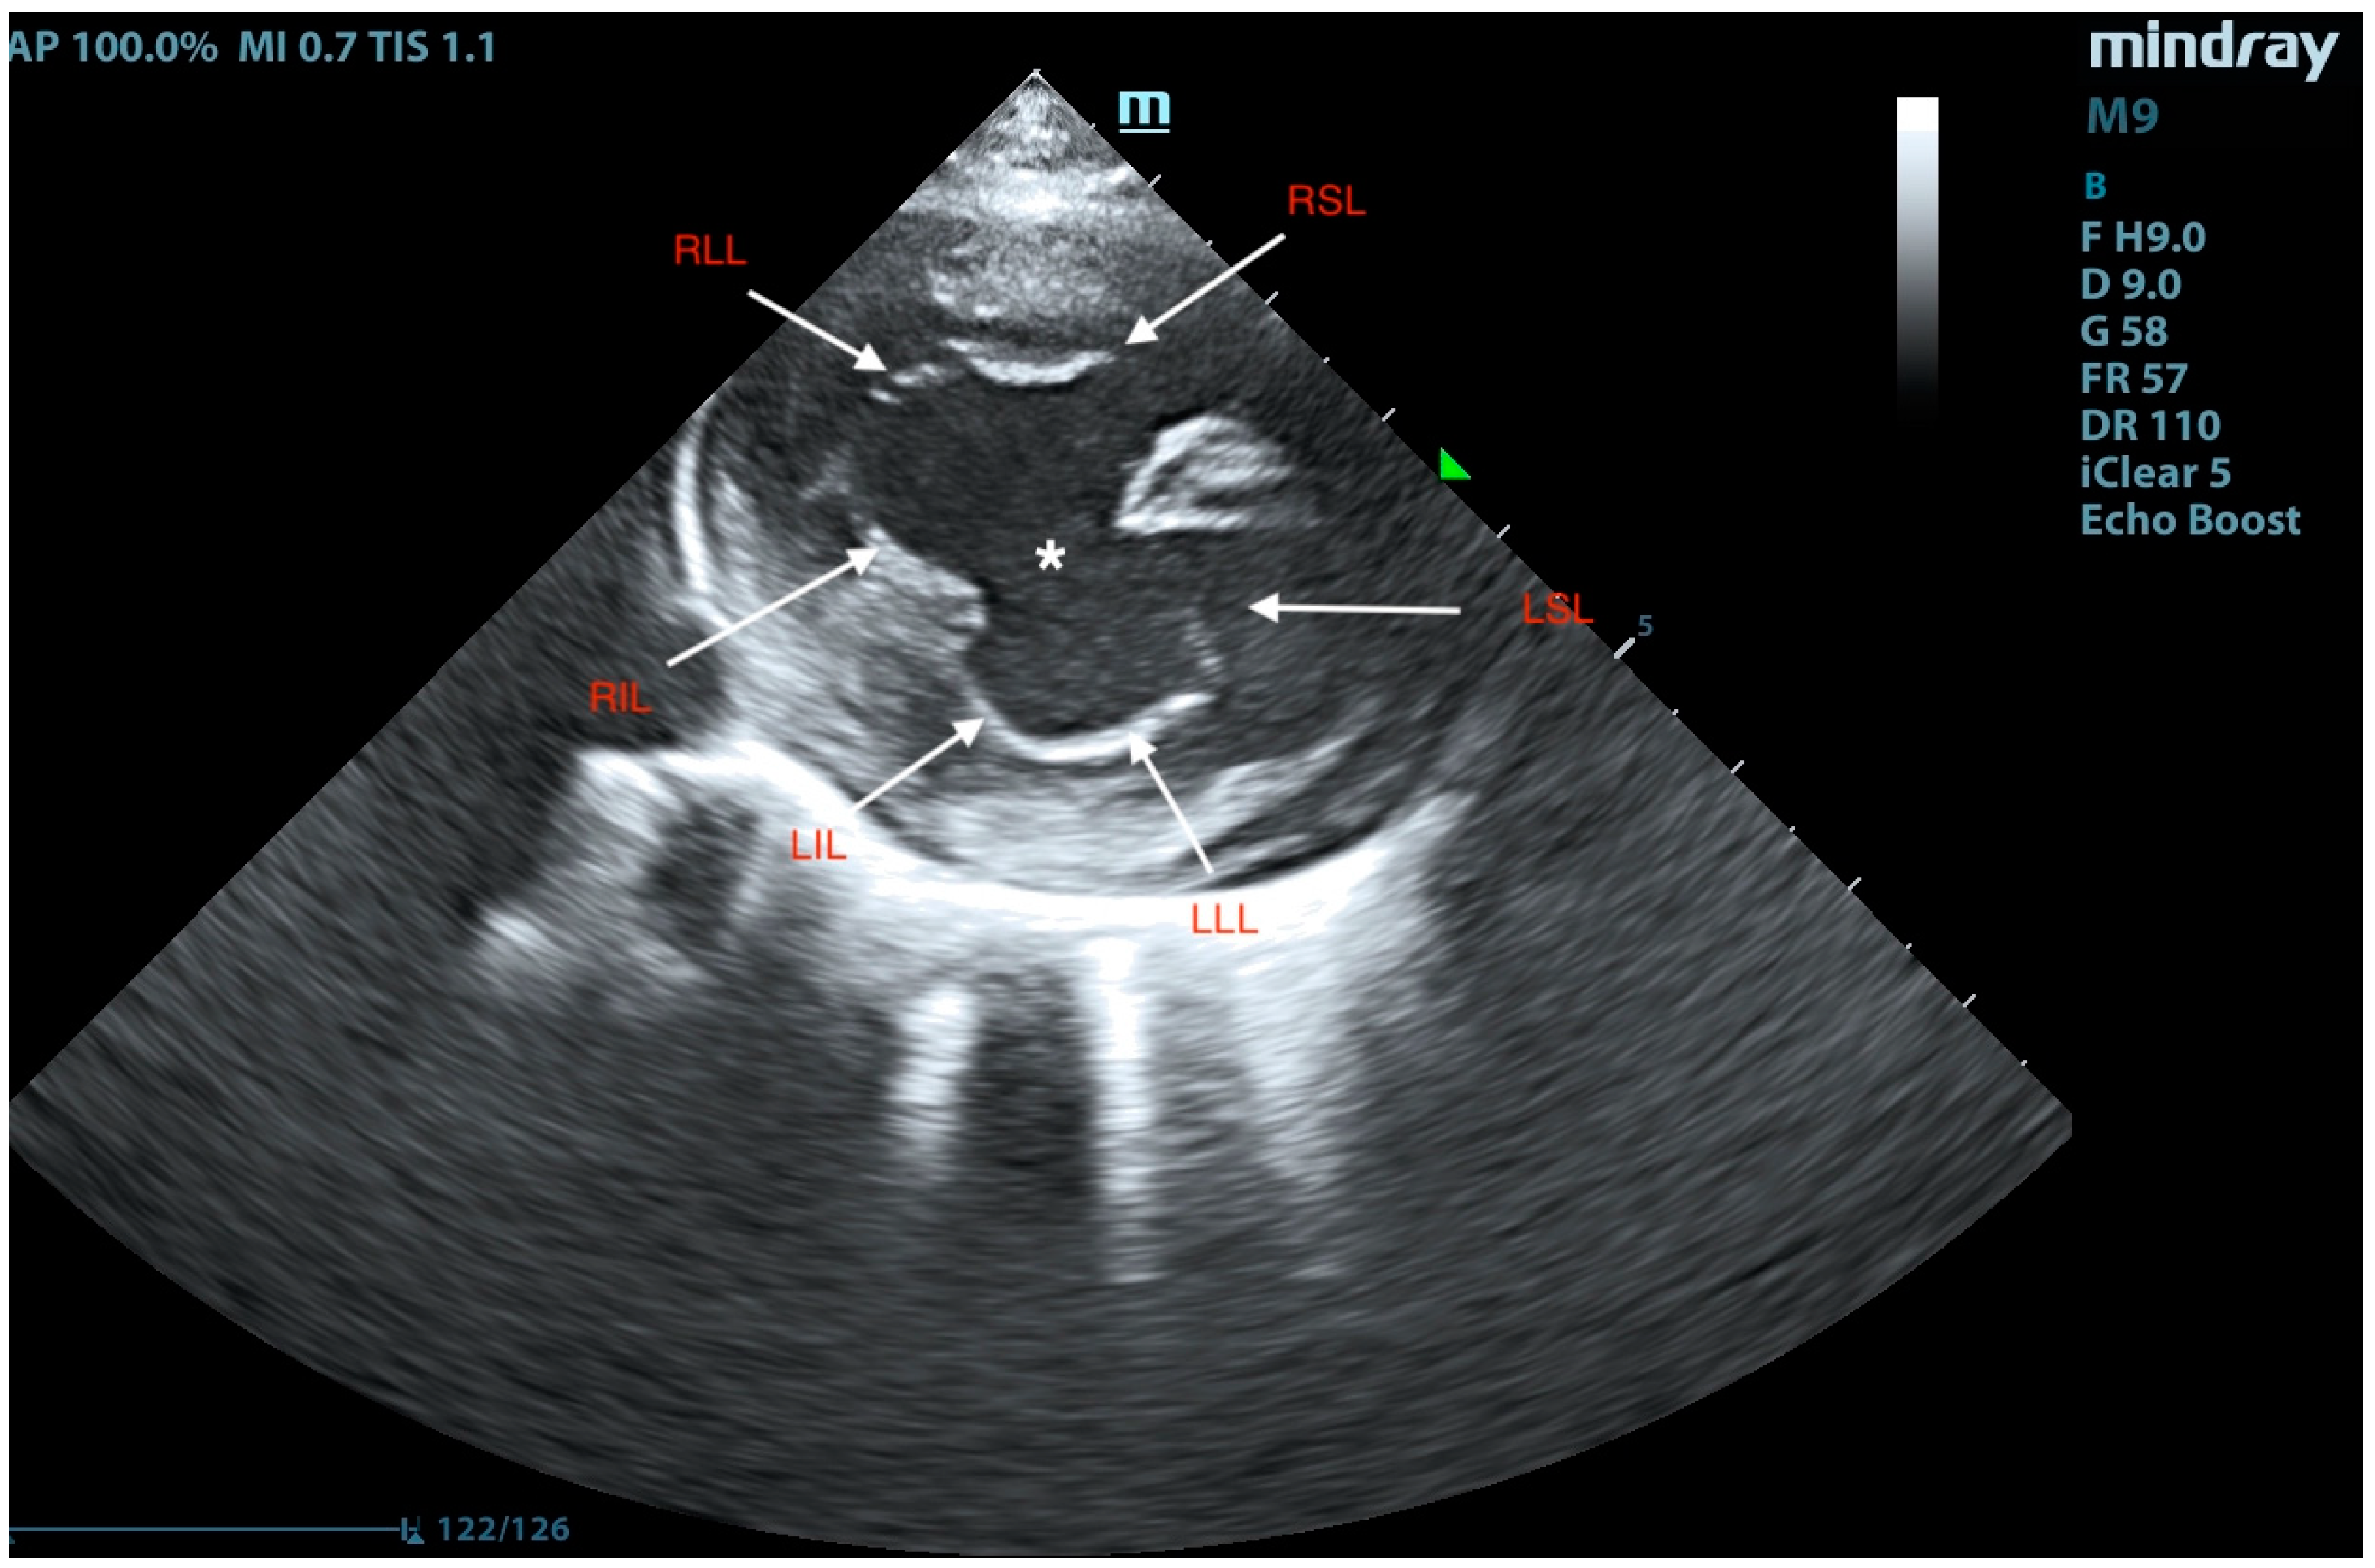

2. Case Presentation